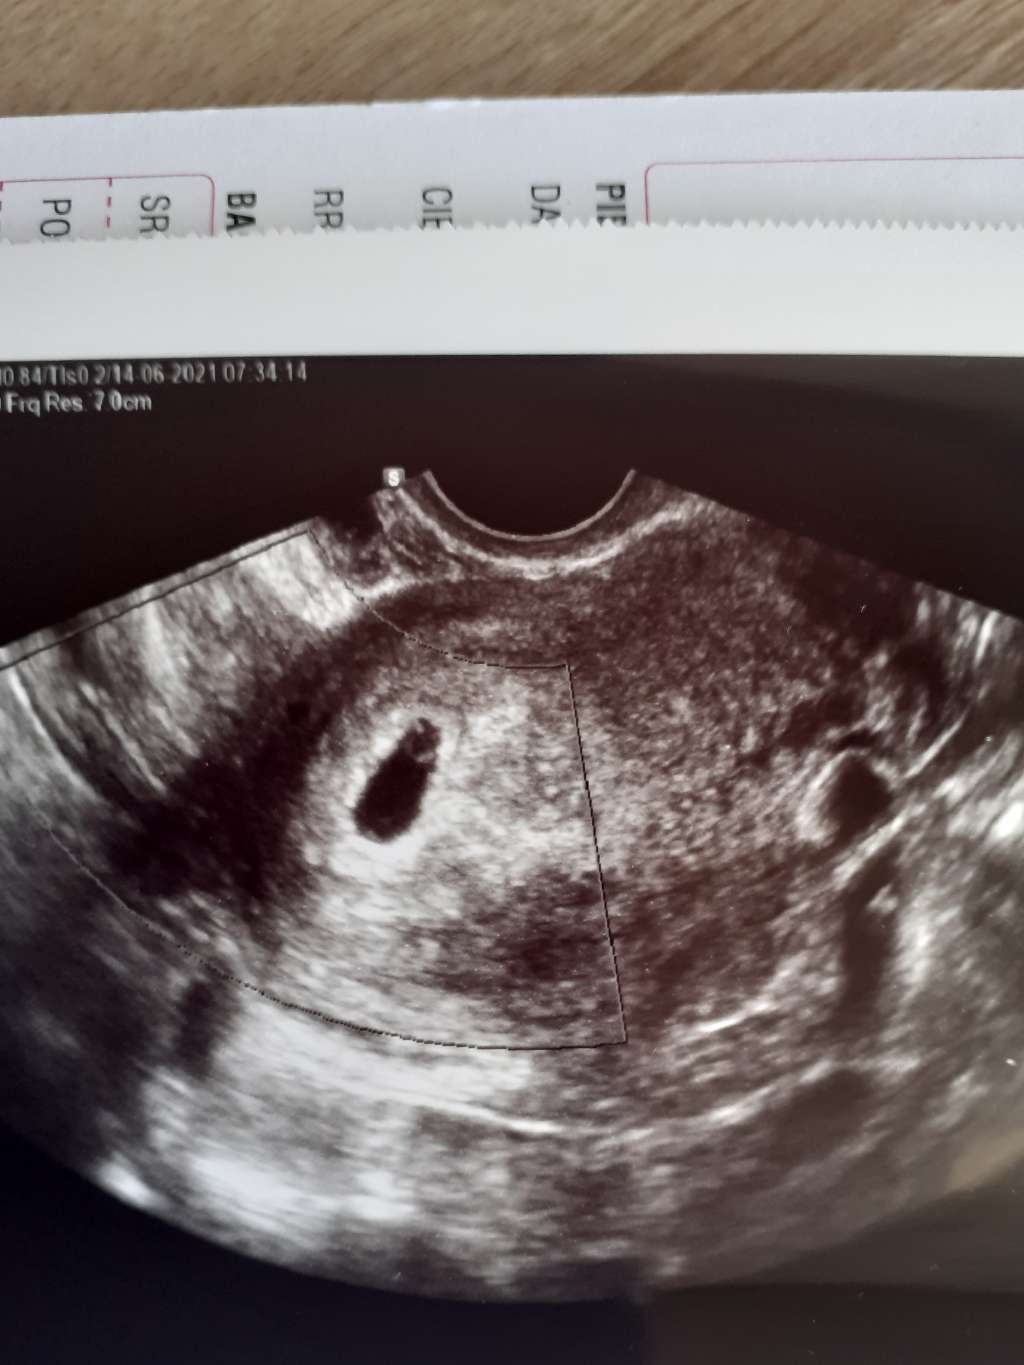

Hej dziewczyny , byłam tydzień temu nie było nic widać

Byłam dzisiaj 5+5 I takie zdjęcie

Nie było nic mierzone , ponieważ to była bez płatna wizyta, taka by tylko by sprawdzić czy pęcherzyk się pojawił